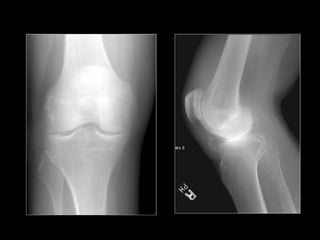

AP radiograph of the knee in a child with hyperparathyroidism shows subperiosteal bone resorption ( arrow) along the proximal medial tibia.

AP radiograph ofthe knee in a child with hyperparathyroidism shows subperiosteal bone resorption ( arrow) along the proximal medial tibia.

• Subperiosteal resorption - M/C

– Usually occurs in the hands and feet.

– M/C affected site: radial aspects of the middle phalanges.

– Acro-osteolysis or phalangeal tufts resoption may also be

present.